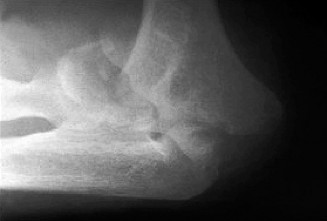

A 65-year-old female with a history of osteopenia presents complaining of hindfoot pain for the past 2 years.…

A 52-year-old female presents to you reporting left foot pain that has been present for the past 3 months. Sh…